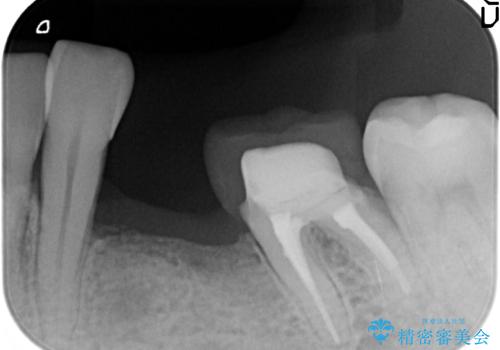

- 左下の歯並びが悪く、左側で物が咬みにくいので診て欲しいといらっしゃった方の症例です。

歯列矯正は御希望されなかったため左下4、5番目の歯を抜歯し、インプラントによる欠損補綴を行いました。

左下6も再根管治療後、オールセラミッククラウンによる補綴を行いました。